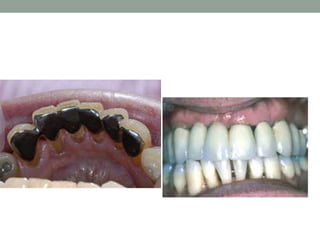

Examples of the mutilation of occlusion

associated with unreplaced missing

teeth.

Note pronounced pathologic migration,

disturbed proximal contacts, and

functional relationships with closing of

the bite.

Maxillary incisors pushed labially in a patient

with bilateral unreplaced mandibular molars.

Note the extrusion of the maxillary molars.

Examples of themutilation of occlusion associated with unreplaced missing teeth. Note pronounced pathologic migration, disturbed proximal contacts, and functional relationships with closing of the bite.

Maxillary incisors pushedlabially in a patient with bilateral unreplaced mandibular molars. Note the extrusion of the maxillary molars.